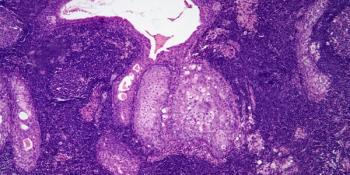

A 42-year-old woman presents with excess uterine bleeding. After a biopsy is performed, what is your diagnosis?